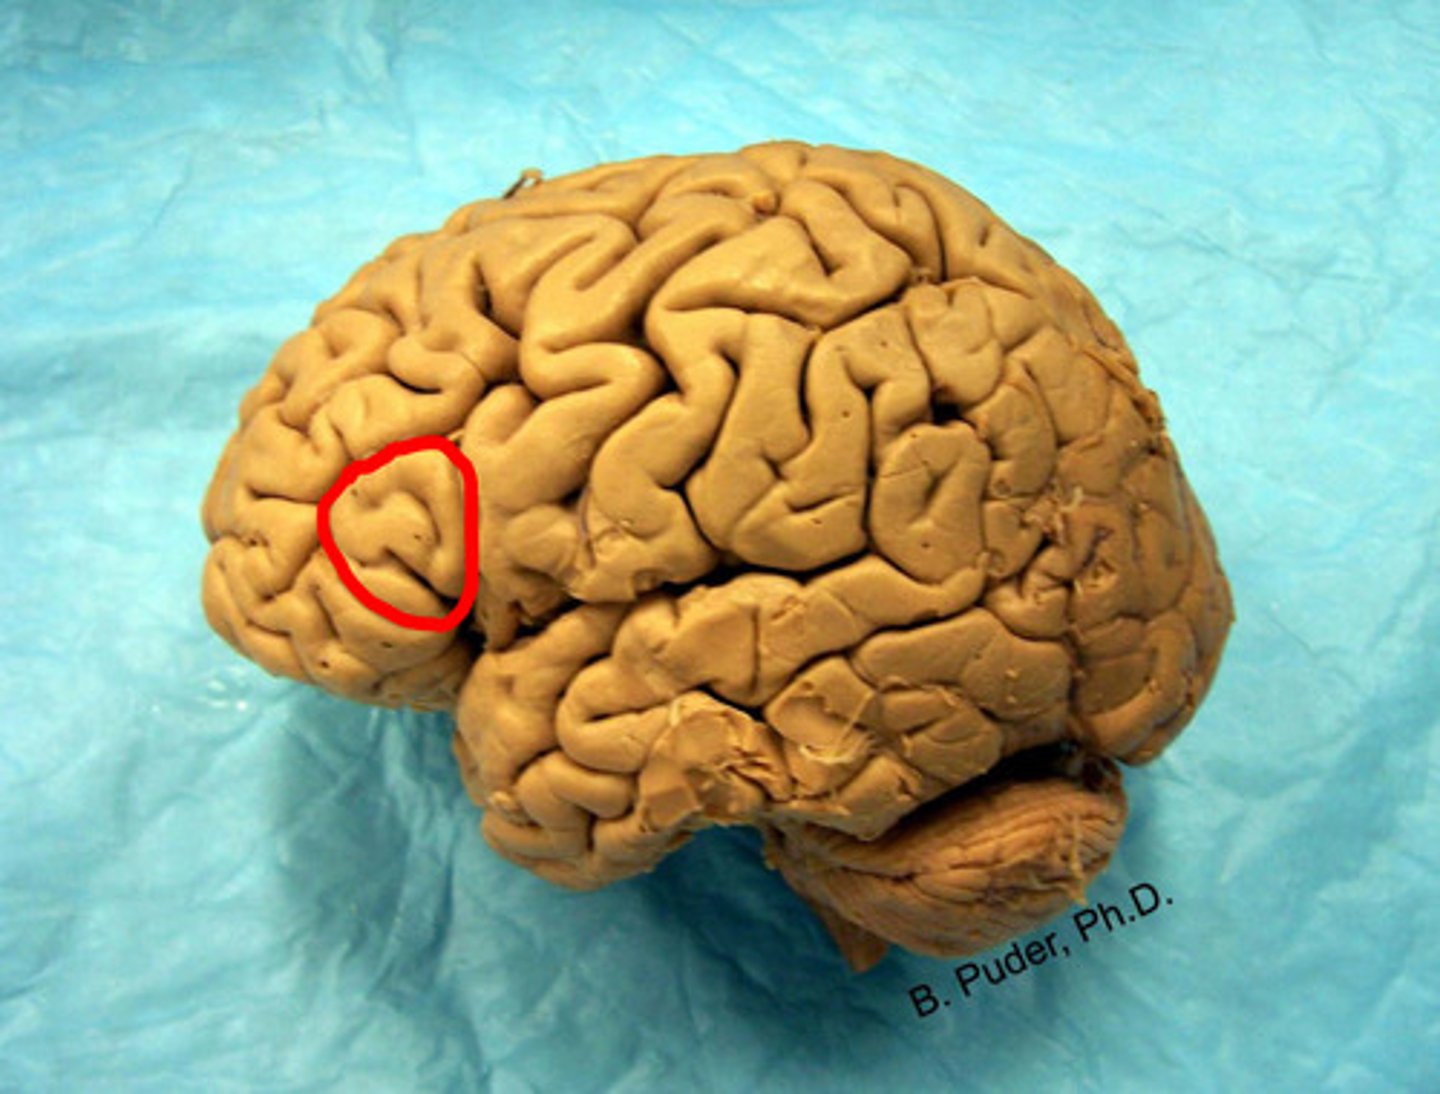

pre-central gyrus

label

broca's motor speech area